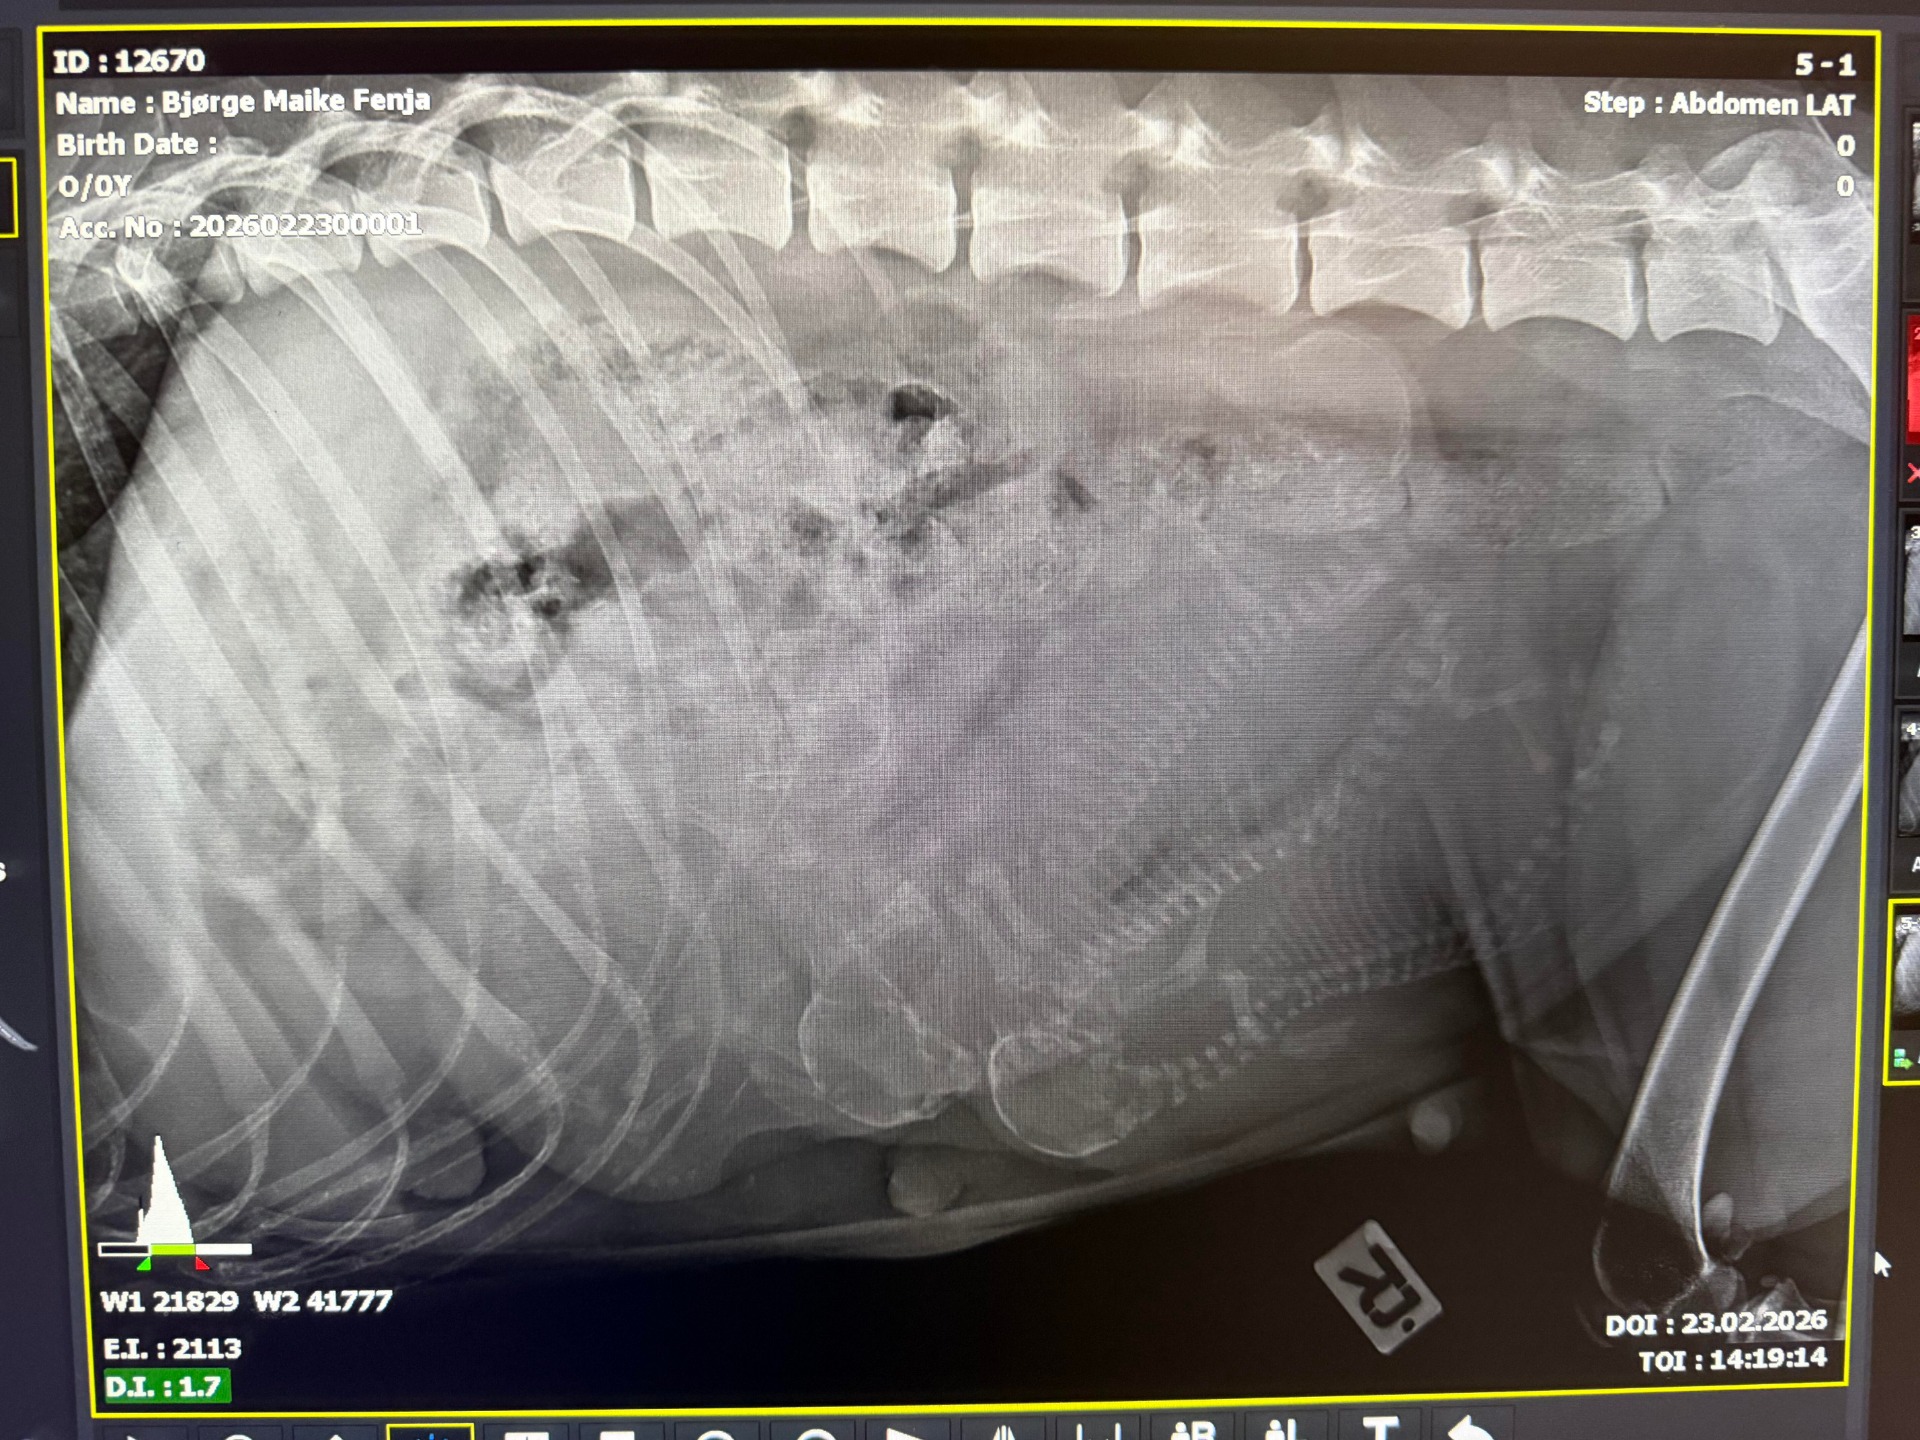

Det første bildet av A-kullet vårt. Fire valper viser seg tydelig på røntgenbildet.

Jaani vom Dreyer Wittsand (Fenja) ble parret med Barnabas vom Trentelberg (Ben) på 31.12.2025 og 02.01.2026.

Det er spennende å komme i gang med kennelens første kull!